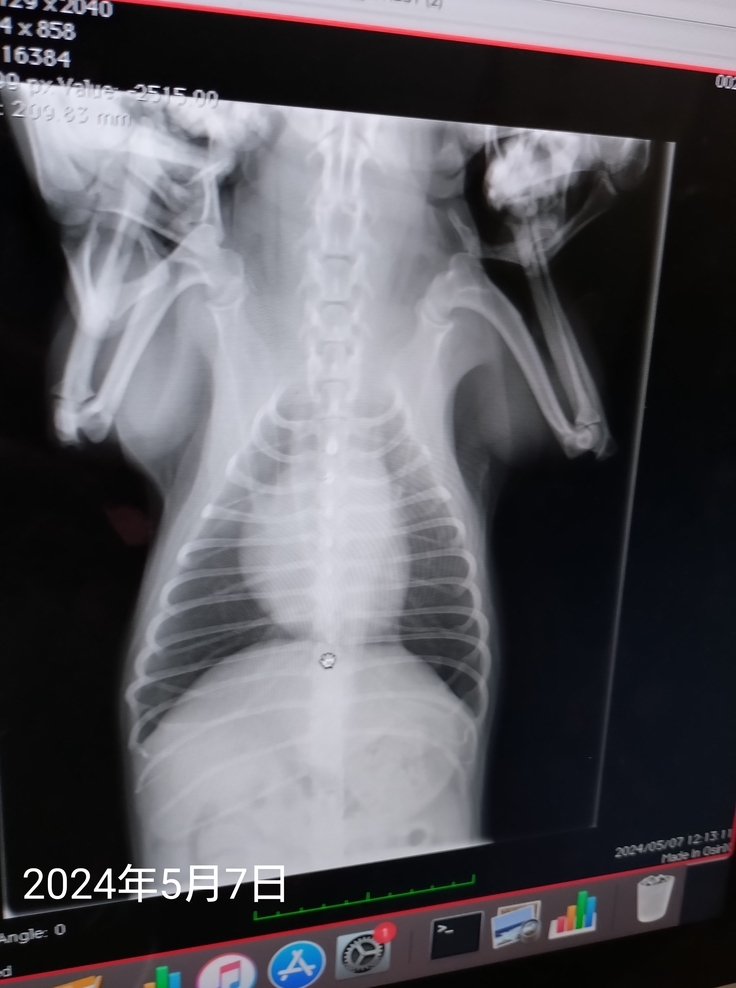

6月22日にかかりつけ病院を受診し、肺の音、心臓の音は前に肺水腫、肺炎、気管支炎、扁桃炎になったときと比べ、肺などは問題ない状態でした。

レントゲンも5月に検査した結果と見比べても問題なく、血液検査の結果、CRPの数値が少しだけ高い状態でした。(肺水腫、肺炎ひどかったときは白血球の値も異常、CRPの数値も7で振り切れてたが、今回1.1)どこかに炎症が起きてる可能性は否めない数値でした。